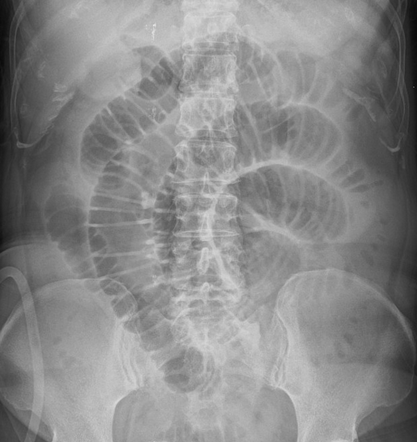

Plain abdominal radiographs. Small bowel loop distension. Red arrow — Radiopaque mass (gallstone) (Courtesy Dr. V. Penopoulos)